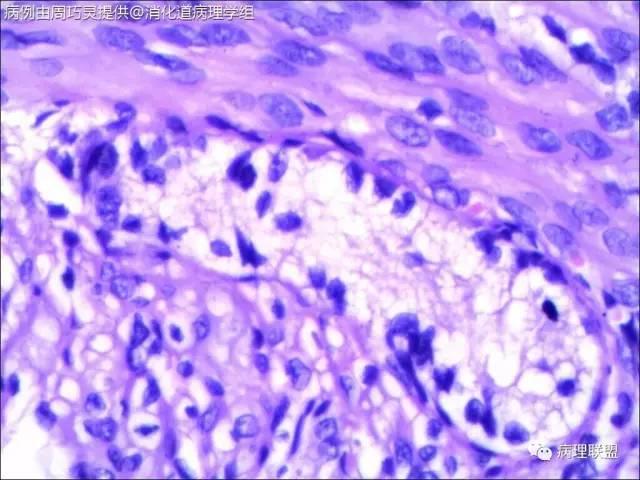

引产胎儿,小肠扩张,肠管回盲部以下直径<回盲部以上。取回盲部及升结肠肠壁镜检。(病例由周巧灵提供,致谢!)

请教各位老师,这些神经节是否正常?是先天性巨结肠吗?正常胎儿的神经节细胞也是核大核仁大的细胞吗?

@石雪迎 石老师,取的就是扩张肠管远端狭窄处,刚好就是回盲部。我在肠壁中见到比较多的神经节,但是里面很少见正常成熟的神经节细胞,应该是支持巨结肠的。不过,我不知道,胎儿时期肠壁正常的神经节是啥样子,所以,不太敢确定,还请老师指点。

这是我在图片中仅见的几个节细胞

@周巧灵 抱歉看错了,以为是结肠扩张。不知道是多大周数引产的胎儿?理论上4个月的胎儿肠神经丛就完成从近端到远端的分布,但直到出生,神经节里的都有不成熟的节细胞。您的图片里确实大部分都没有成熟神经元,但有的似乎不能排除有不成熟神经元,可以染NSE看看,如果还有,诊断HD就没有依据了。中华病理杂志曾经发表过何乐健教授等写的一篇HD病理诊断规范,尤其是有关取材的建议很实用,不妨参考一下